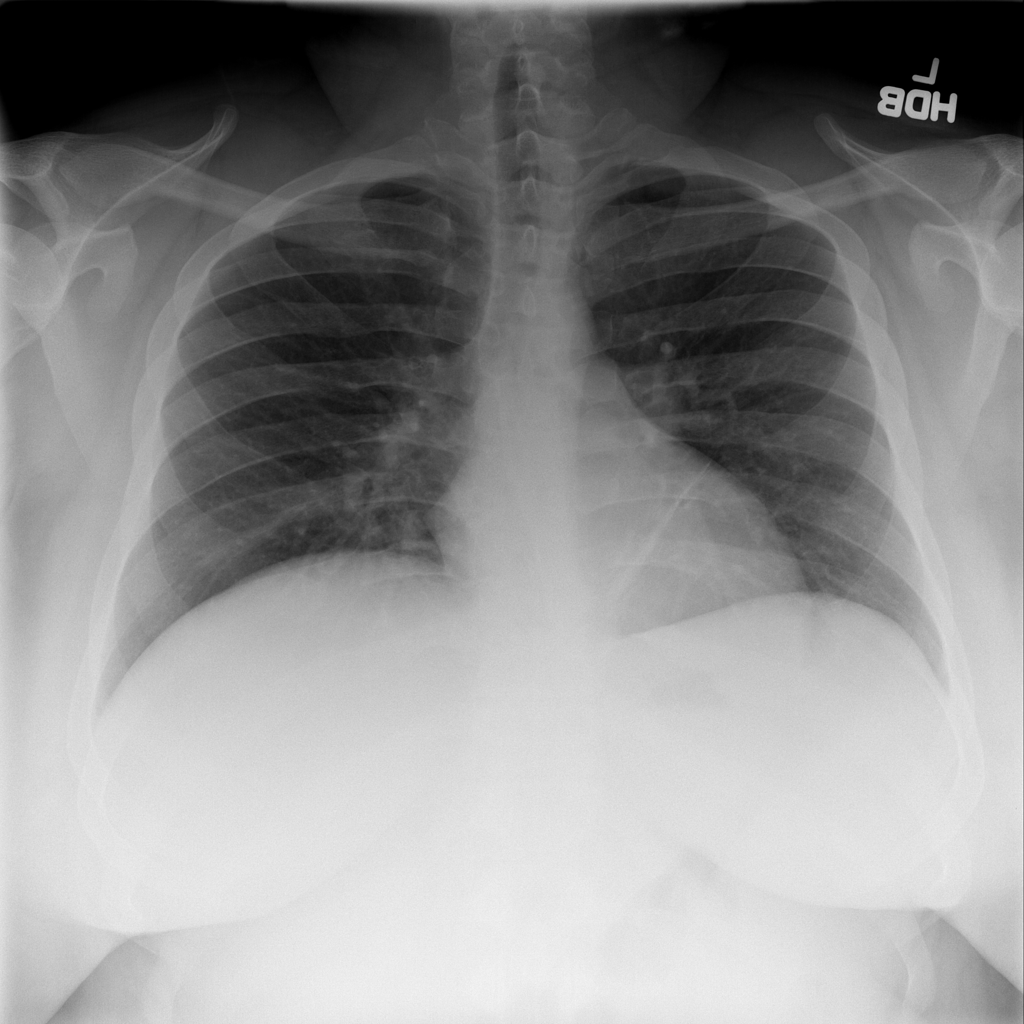

PAT-C77C · IMG-003Fibrosis

PAT-C77C · IMG-003

PA